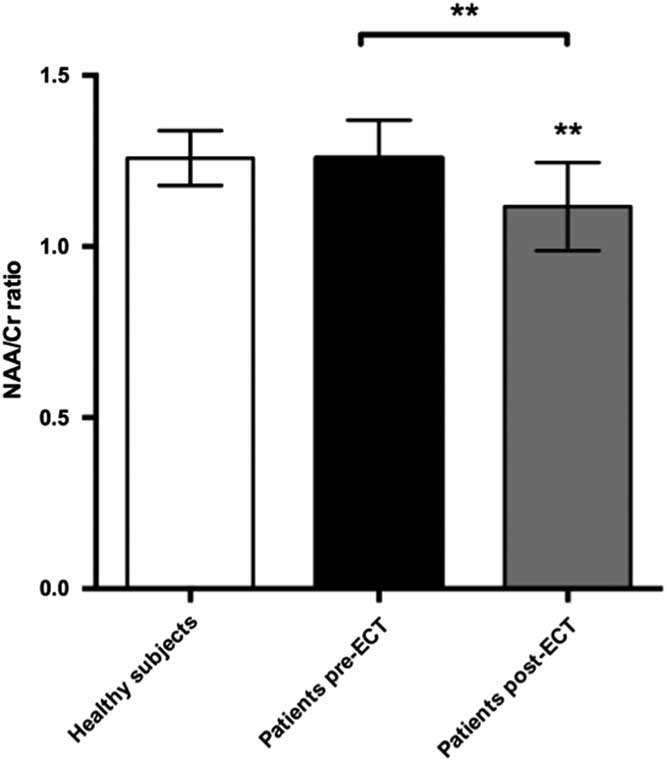

Other metabolites of interest

We found a significant decrease in the NAA/Cr ratios in the PFC during ECT, t(22)=3.89, p=0.0038. Cohen’s d was 1.18, representing a large effect size. This was still significant after a Bonferroni correction for the six tests made on prefrontal changes with ECT (giving a corrected p-value of 0.08). There was no significant difference when comparing baseline NAA/Cr levels between patients and healthy subjects. However, post-ECT NAA/Cr ratios were significantly lower in patients compared with healthy subjects, t(21)=2.9, p=0.007 (Fig. 5). Cohen’s d was 1.36. Finally, we found a significant correlation between numbers of ECT sessions and NAA/Cr change (p=0.035), with NAA/Cr ratios decreasing as the number of ECT sessions increased.

Fig. 5 Plot of NAA:Cr ratios in prefrontal cortex showing mean ± SD. ECT, electroconvulsive therapy; NAA, N-acetylaspartate.

To investigate whether the observed difference in NAA/Cr was caused by differences in GM content within the voxel we compared the fraction of GM from the segmented T1 image between healthy subjects (GM 0.56±0.05) and patients at baseline (GM 0.53±0.06), but found no significant difference (p=0.37). Also, post-ECT GM content (GM 0.55±0.06) did not differ significantly from baseline (p=0.35). Due to technical issues segmentation was only performed in nine patients and 11 healthy subjects.